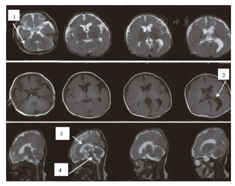

先证者,男,就诊时3个月。第2胎,第1产(第1胎自然流产),足月,孕期胎动少,因胎位不正、脐带绕颈剖宫产娩出,生后窒息(具体不详),哭声弱,肢体无力,3个月不会抬头,不会蹬被,可追光追物,逗笑差。就诊时体格检查:头围32.5 cm,肝肋下2.5 cm,脾未及,患儿消瘦,头左右活动差,四肢肌张力减低,肌力差,近端著,双膝关节、踝关节挛缩,双膝腱反射未引出,病理征(-)。眼科检查提示角膜大,疑诊青光眼。血清肌酸激酶(CK)2次检查结果分别为2 274.5 U/L和2 122.0 U/L,;心电图及超声心动图未见异常;头颅磁共振(MRI)示侧脑室扩大,小脑、脑干发育不良,胼胝体发育不良,小脑囊肿(图1)。本研究获患者家属的知情同意,并经医院伦理委员会讨论通过。

Brain magnetic resonance imaging of the patient with Walker-Warburg syndrome

注:1:小脑囊肿;2:侧脑室扩大;3:胼胝体发育不良;4:脑干、小脑发育不良 1:cerebellum cyst;2:extensive ventricles;3:corpus callosum dysplasia;4:dysplasia in the brainstem and cerebellum